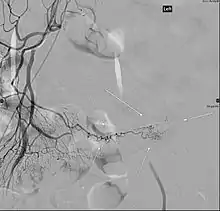

Angiography of a Meckel's diverticulum that presented with bleeding.

Angiography might identify brisk bleeding in patients with Meckel's diverticulum.[17]